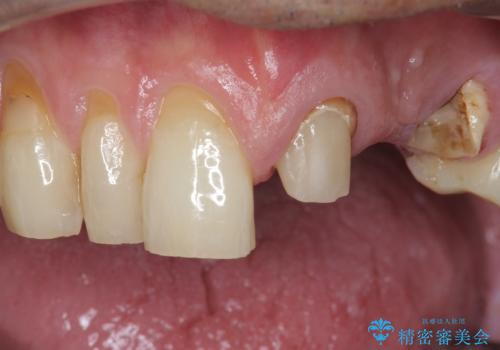

歯の牽引後、ブリッジの仮歯で保定しながら歯肉・骨の治癒を待ったのち、ブリッジによる補綴を行いました。

根の長さが短くなるためブリッジの支台歯としては弱いこと、長期的予後は不明なことをご理解頂いた上で治療を行いました。

根管治療はご希望されず行っておりません。